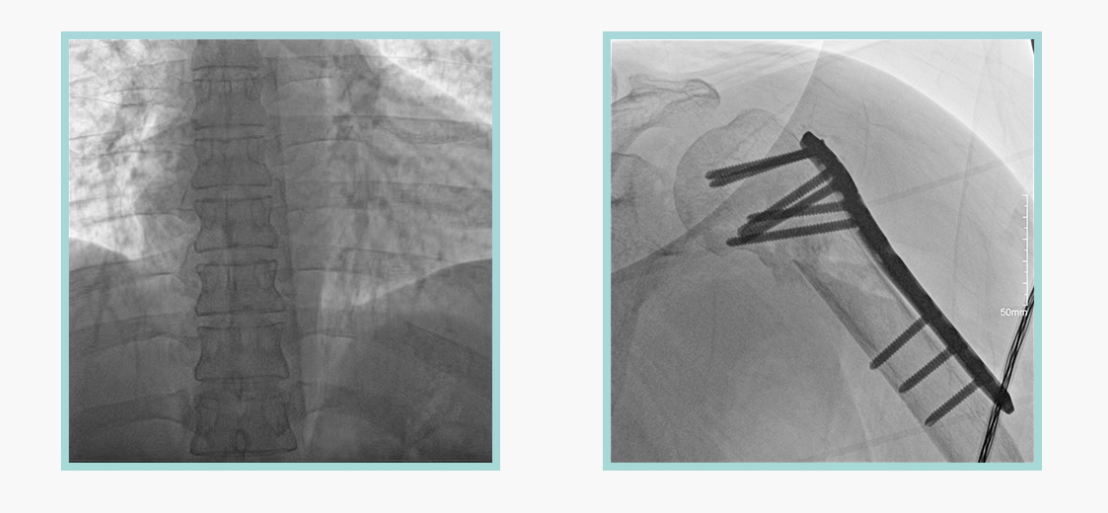

太阳成集团tyc122cc入口科技悦画移动C臂X线摄影系统,采用了业内技术最尖端的CMOS探测器。基于性能优异的针状CSI闪烁体涂层和高灵敏度的CMOS感光芯片,悦画可以实现在超低X线剂量条件下实现高清晰影像成像,相较于一般的影增移动C臂和平板C臂,动态范围更高,影像的层次感和对比度更好。

在产品的性能参数设计上,悦画的像素可达到200万,空间分辨率可达到3.2线对,采用16bit的影像灰度,悦画在影像后处理上,通过SPI金字塔图像算法,支持摄影、脉冲透视影像、连续透视等多种模式下的影像采集,动态透视影像视频支持保存与回放。双大屏的设计,透视影像支持三档放大,保证临床影像读取的便利。

悦画在影像的伪影处理上,也积累多项图像处理专利技术。通过对植入物的精准识别,悦画能够精准祛除植入物伪影与运动伪影,保证高质量的影像输出,无论是影像的对比度、分辨率(清晰度)相较于市面上的移动C臂产品都更胜一筹。